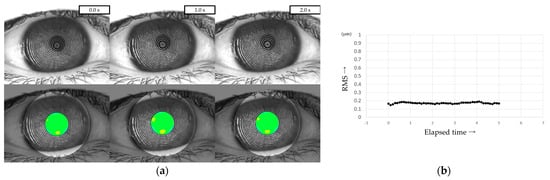

All patients were instructed to keep their eyes open for at least 5 s, and MR images were captured on video using a VK (RET-700; Rexxam Co., Ltd., Osaka, Japan) at 10 frames/second. The obtained MR image data was used for calculating corneal curvature, and aberrations between the ideal wavefront and that obtained from the calculated corneal curvature were analyzed with a Zernike polynomial using custom-made analysis software. HOAs were then calculated as the root mean square (RMS, in µm) of the wavefront deviation at a 4-mm pupil diameter (Figure 1). This custom-made analysis software is incorporated into the software used in our previous study of DED evaluation using VK [32].

Figure 1.

Measurement of HOAs using VK. (a) Upper column: MR images obtained via VK. Lower column: HOAs calculated from MR images. MR images were analyzed with a Zernike polynomial, and the HOAs were described as the RMS (µm) of the wavefront aberrations at a 4-mm pupil diameter. (b) HOAs evaluated every 0.1 s were automatically graphed, allowing for the evaluation of changes over time.

HOAs were evaluated every 0.1 s from immediately after eye opening (0 s) to 5 s after eye opening. For frames in which the HOAs were difficult to measure due to momentary eye movements, the same values as in the frames immediately before or after were used, considering the sequential dynamics of the TF. The HOAs at the time points immediately after eye opening (i.e., 0 s), 1 s, 2 s, 3 s, 4 s, and 5 s after eye opening were defined as HOAs(0), HOAs(1), HOAs(2), HOAs(3), HOAs(4), and HOAs(5), respectively.